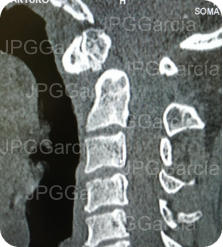

Imágenes de tomografía la unión cráneo cervical que muestra un fractura de la apófisis odontoides llamada “os odontoideo”